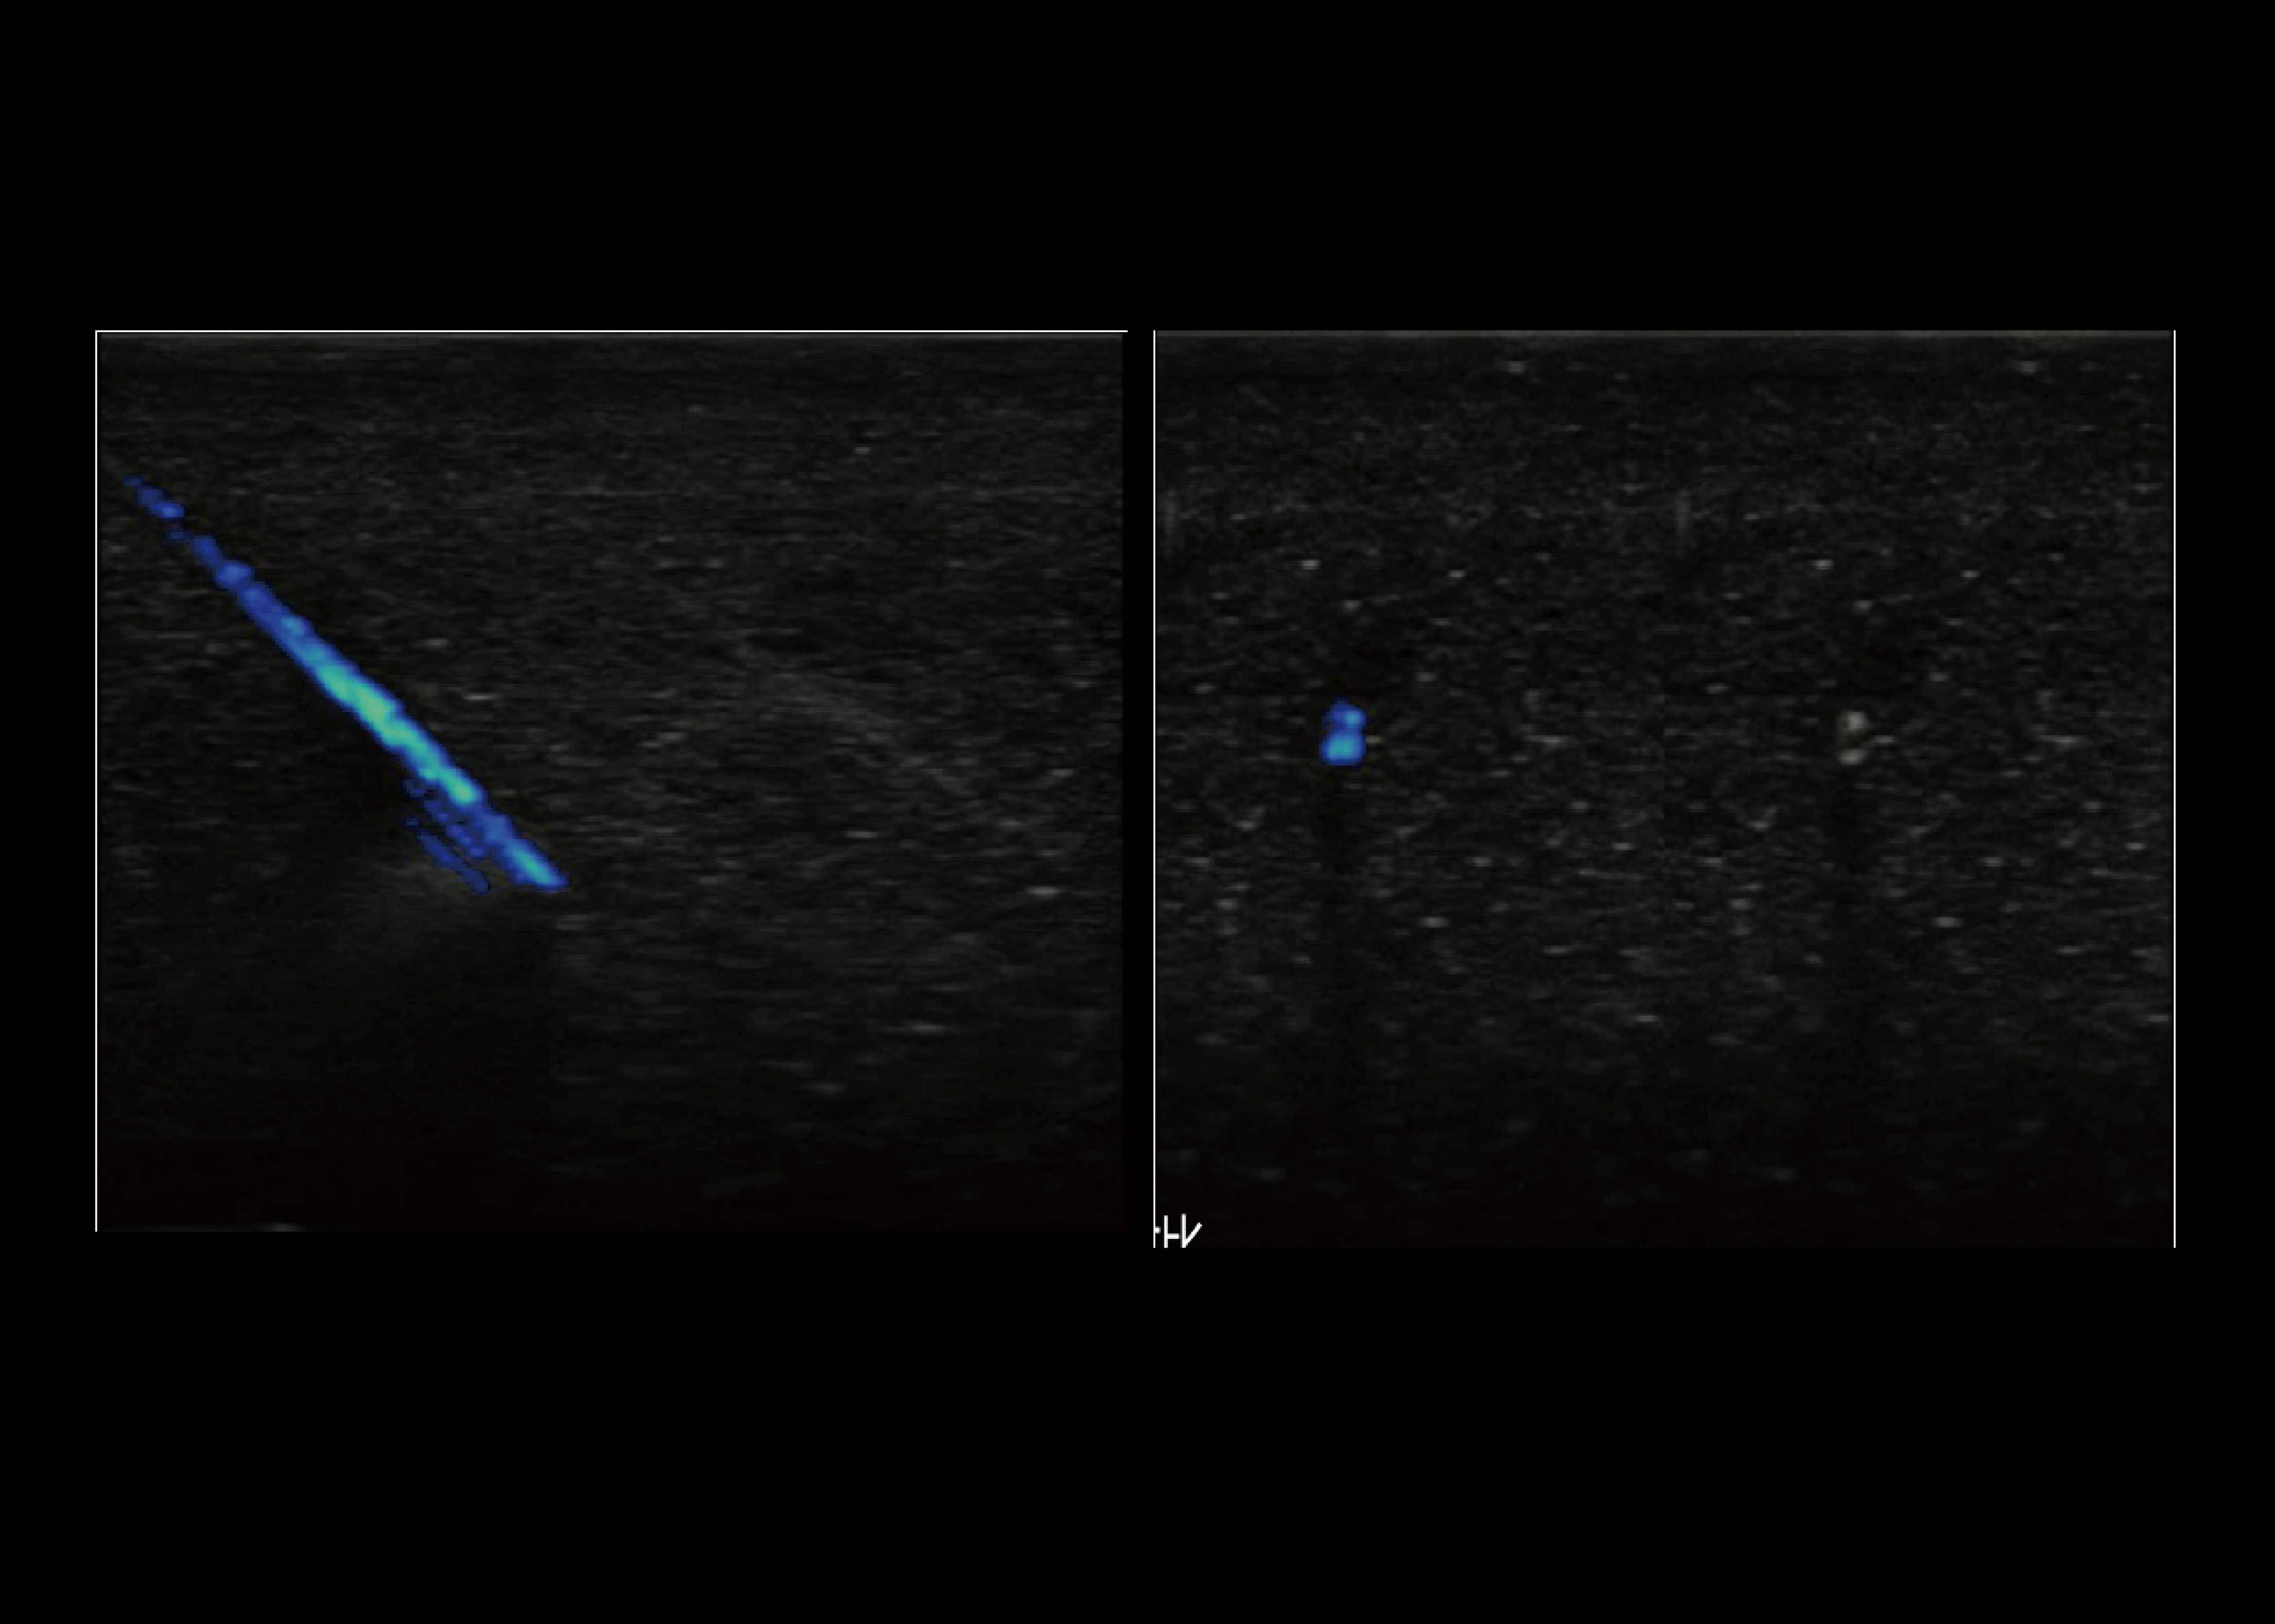

MVI

● Dabei wurde ein völlig neuer Algorithmus zur Überprüfung des Blutflusses angewandt.

● Deutliche Verbesserung der Visualisierungssensitivität bei niedrigen Geschwindigkeiten und kleine Blutgefäße.

● Mehr und genauere Informationen über den Blutfluss für die Klinik bereitstellen.

SonoNeedle

● Die SonoNeedle-Funktion ist eine hochmoderne Ultraschalldiagnose Punktionsnavigationssystem. In diesem Modus wird der Nadelweg und Die Position der Nadelspitze wird dynamisch und in Echtzeit in Farbe angezeigt.

● Es kann die Effizienz und Genauigkeit der Punktion verbessern.